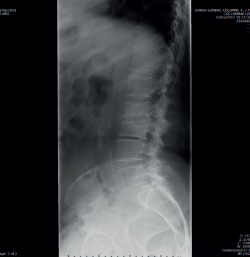

Figura 1. Radiografías de frente y de perfil lumbares.

• La radiología simple lumbar (Figura 1) de frente y de perfil muestra grave discopatía L2/L3 con práctica desaparición del disco intervertebral.